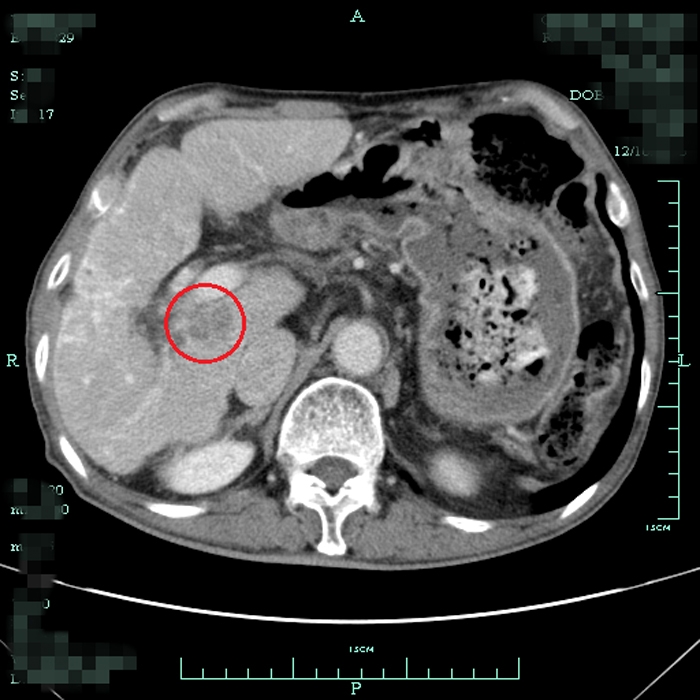

患者術(shù)前尾狀葉腫塊CT顯影

?? 據(jù)我院肝膽外科方劍醫(yī)生介紹,肝尾狀葉位于肝后下腔靜脈的前方,第一肝門的后方,三支肝靜脈的下方,亦即夾于三個肝門狹小空間之中,位置深,顯露困難,被認(rèn)為是肝臟手術(shù)的“最后禁區(qū)”。

?? 手術(shù)切除是尾狀葉腫瘤的主要治療方式。但由于其位置特殊,手術(shù)難度高,創(chuàng)傷大,風(fēng)險極高。困擾他們一家的問題還不止這些,毛大爺原有肝硬化病史和肺癌手術(shù)史,高昂的手術(shù)費(fèi)用和較長的住院時間也成了加重家庭負(fù)擔(dān)的現(xiàn)實問題。有沒有一種治療效果與手術(shù)相近,而創(chuàng)傷更小、住院時間更短的治療方法呢?肝膽外科的醫(yī)生團(tuán)隊討論后決定采用射頻消融術(shù)來治療毛大爺?shù)奈矤钊~腫瘤。